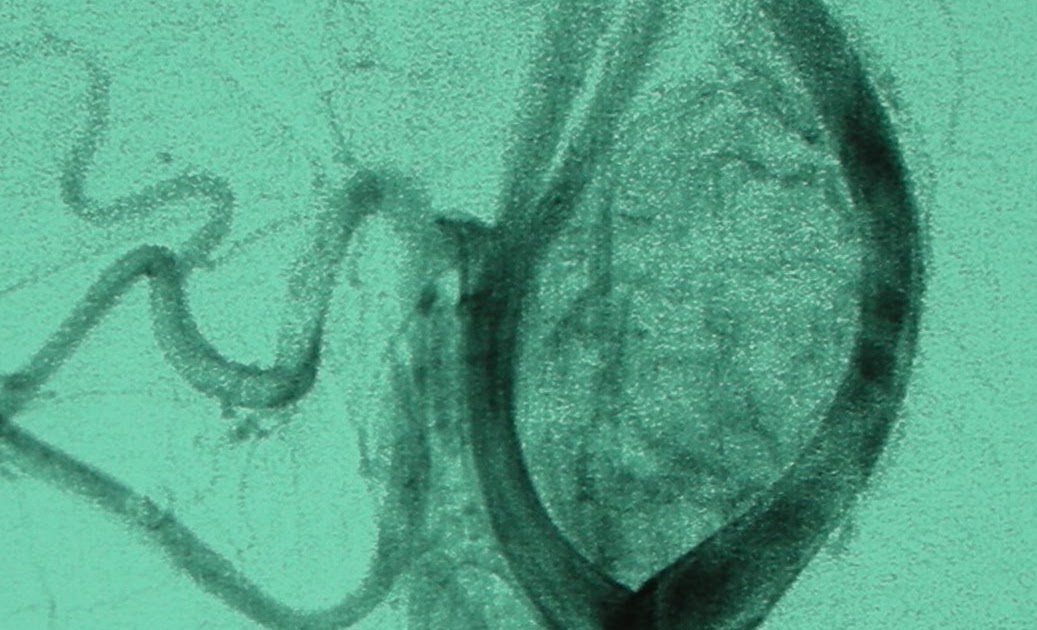

Los tumores del glomus carotídeo son lesiones de crecimiento lento, hipervascularizados, infrecuentes, derivados de células paraganglionares de la cresta neural y que representan casi la mitad de los paragangliomas.